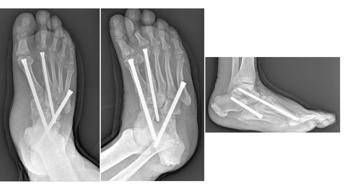

(Adnkronos) – Uno dei più temibili nemici del piede è una grave e rara complicanza del diabete, un capitolo del cosiddetto piede diabetico, con un nome complesso: la neuro-osteoartropatia di Charcot. Il Policlinico universitario Gemelli Irccs di Roma è una delle poche strutture italiane dove è possibile gestirla da un punto di vista internistico e diabetologico ed effettuare i complicati interventi di salvataggio ortopedico di questi piedi deformati e disabilitati dalla malattia. Sono molteplici gli interventi eseguiti al Gemelli ogni anno per restituire la possibilità di camminare, scongiurando il rischio amputazione, a diverse persone con diabete. Se intercettata precocemente, la malattia non progredisce verso la fase cronica, quella appunto delle deformità articolari. Ma per questo è necessario un occhio esperto, quello del diabetologo. "Condizione predisponente del piede di Charcot – spiega Dario Pitocco, associato di Endocrinologia all'università Cattolica del Sacro Cuore Campus di Roma e direttore della Uosa di Diabetologia della Fondazione Policlinico Gemelli – è la neuropatia diabetica, che comporta un grave quadro di disregolazione infiammatoria, concentrato a livello del piede. Ma questa è solo una parte della storia. La neuropatia è importante, ma non basta da sola e le vere cause del piede di Charcot di fatto non sono ancora note. Potrebbe giocare un ruolo anche una predisposizione genetica sulla modulazione del metabolismo dell'osso". A essere affetto da neuropatia è almeno il 30-40% delle persone con diabete; il piede di Charcot compare solo nello 0,05% dei casi. Parliamo dunque di una malattia rara.  "Questi pazienti – prosegue Pitocco, co-autore anche di una Consensus dell'American Diabetes Association sull'argomento – hanno una grave disregolazione dei processi infiammatori, anche a seguito di uno stimolo banale come il sovraccarico sul piede. Molto spesso sono colpite persone che passano molto tempo in piedi (camerieri, cuochi) o che utilizzano molto il piede come gli autisti. Il fatto che la neuropatia attutisca il dolore, che in genere è un importante campanello d'allarme, fa sì che la diagnosi sia tardiva. Nelle fasi iniziali (acute) il piede appare rosso, gonfio, caldo, ma non è presente dolore. Un occhio non esperto può scambiare il quadro per una vasculite, per un trauma o per gotta. Oltre alla visita specialistica diabetologica, che permette di porre il sospetto diagnostico, un esame strumentale importante nella fase acuta è la risonanza magnetica, che evidenzia edema della spongiosa dell'osso. Una semplice radiografia nella fase iniziale, invece, non consente di fare diagnosi. In questa fase l'approccio terapeutico più efficace è il riposo; il paziente non deve caricare su quel piede (vengono utilizzati speciali tutori per evitare il carico)". Se questa fase diagnostica viene mancata, la malattia progredisce anche rapidamente (pochi mesi) verso la fase cronica, quella delle complicanze che richiedono l'intervento dell'ortopedico. E non solo. La gestione del piede di Charcot richiede un'équipe multidisciplinare, perché oltre al diabetologo e all'ortopedico spesso è necessario l'intervento del chirurgo vascolare, dell'infettivologo, del chirurgo plastico, del dermatologo, del fisioterapista e di tanti altri specialisti. "Nel piede di Charcot – descrive Carlo Perisano, ricercatore in Ortopedia e Traumatologia all'università Cattolica Campus di Roma e dirigente medico presso la Uoc di Ortopedia e Traumatologia del Policlinico Gemelli – assistiamo a una progressiva alterazione dei tessuti molli, delle articolazioni e delle ossa del piede, che vanno incontro a un marcato riassorbimento e a molte microfratture che portano all'instaurarsi delle deformità. Il piede si deforma fino a diventare un 'piede a dondolo' (in inglese 'rocker bottom foot deformity'), a causa della mal consolidazione dell'osso e a una stabilizzazione di quella deformità che determinano una serie di sequele". Queste, in stadio avanzato, possono essere corrette solo da un complesso intervento, che di fatto diventa una chirurgia di salvataggio dell'arto.  "Sono interventi che mirano a correggere deformità estremamente complesse del piede e della caviglia – illustra Perisano – e che prevedono una serie di procedure chirurgiche (nell'ambito dello stesso intervento), quali osteotomie correttive e successive osteosintesi. Questo consente la ricostruzione di un asse del piede e della caviglia, per permettere al paziente di tornare a camminare (in genere entro un paio di mesi dall'intervento). I pazienti affetti da questa condizione infatti non riescono più a deambulare perché queste deformità comportano alterazioni dell'appoggio, che sottopongono alcune zone del piede, normalmente non deputate a sostenere il carico, ad una pressione eccessiva che a sua volta può portare ad ulcerazioni; queste, nei pazienti diabetici (che spesso sono anche vasculopatici), possono causare infezioni gravi e profonde, che a loro volta comportano un elevato rischio di amputazione". "Il piede di Charcot – commenta Giulio Maccauro, ordinario di Ortopedia alla Cattolica Campus di Roma e direttore della Uoc di Ortopedia e Traumatologia del Gemelli – è una condizione clinica estremamente invalidante. All'interno della nostra istituzione riusciamo a dare risposte, all'interno di un percorso multidisciplinare, a tutte le persone con piede diabetico, offrendo loro l'intera gamma di trattamenti ortopedici, da quelli convenzionali ortesici agli interventi chirurgici più avanzati".